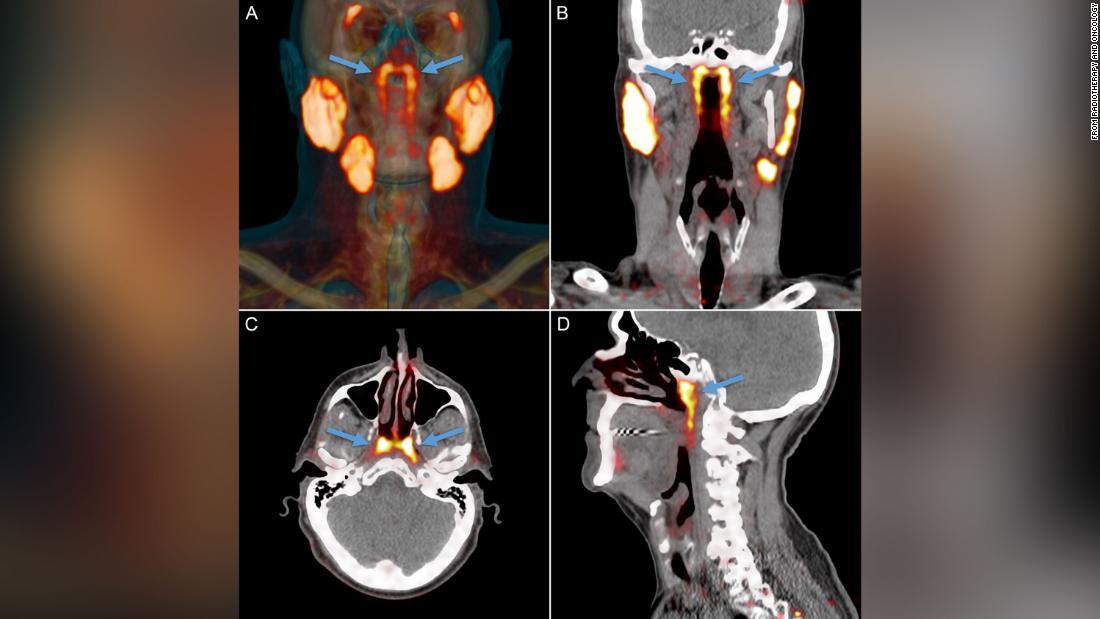

オランダの研究チームが人ののどの奥に未知の臓器を発見した/From Radiotherapy and Oncology

(CNN) オランダの研究チームが、これまでの医学では知られていなかった臓器が人ののどの奥に見つかったとして、このほど医学誌に研究結果を発表した。

発表を行ったのはオランダがん研究所などの研究チーム。鼻腔(びくう)と咽頭(いんとう)がつながる部分の頭蓋骨(ずがいこつ)の中に、未知の腺が隠れているのを発見した。同チームは「tubarial glands」という名称を提案している。

この臓器はがんの転移診断のためのスキャン検査で見つかった。研究チームはさらに、前立腺がんで治療中の患者100人の頭部と頸部(けいぶ)のスキャン画像を調べ、男性1人と女性1人の遺体解剖を行った結果、全員がこの臓器を対でもっていることが分かった。

超音波やCTスキャン、磁気共鳴断層撮影(MRI)といった一般的な検査ではこの臓器は見つけられず、前立腺がんの転移を調べるPSMA PET/CTという先端のスキャン検査で初めて見つかった。

PSMA PET/CTスキャンの画像/From Radiotherapy and Oncology